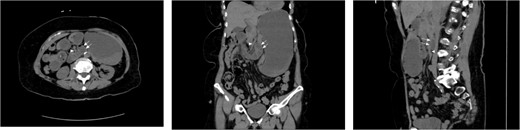

A 59-year-old female presented to our clinic with 10 years of vague episodic abdominal pain without prandial association. These episodes varied in severity, were self-limiting, and were not provoked by any identifiable factor. Her history was significant for asthma, GERD, and previous abdominal hysterectomy. The patient’s abdominal exam revealed only a Pfannenstiel scar but no tenderness, hernia, or palpable mass. The patient did not endorse any active symptoms in clinic. The patient underwent a CT scan of the abdomen and pelvis with IV and PO contrast which demonstrated small bowel loops in the right upper quadrant suspicious for herniation into a left paraduodenal space. Outpatient CT scan images can be found below (Fig. 5). The patient was scheduled for a diagnostic laparoscopy to evaluate for a paraduodenal hernia. Dense and extensive adhesive disease necessitated conversion to an upper midline laparotomy. The patient was found to have a left-sided paraduodenal hernia with the entire jejunum contained within Landzert’s fossa but without any signs of active obstruction. Additionally, the patient was found to have malrotation of the large bowel. After successful reduction of the non-obstructed small bowel, the mesenteric defect was then closed with a running silk stitch and the nearby proximal jejunum tacked over the repair. The malrotated large bowel was also placed in its correct anatomical position. The remainder of the procedure was uncomplicated with the patient recovering well.

CT images for Case 3, axial, coronal, and sagittal, respectively. The isolation of the contrast-filled small bowel can be appreciated in the right upper quadrant, representing bowel entrapped within the left paraduodenal hernia.